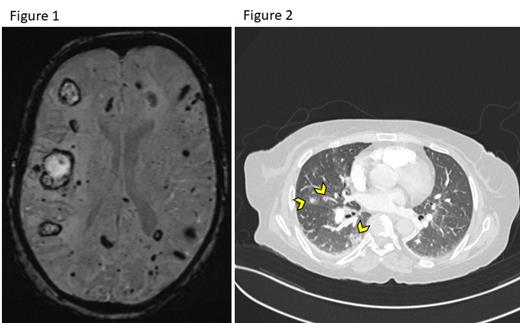

She received first-line therapy with a 5-day course of Cladribine (0.15 mg/kg/day) with initial resolution of leukocytosis, normalization of platelets, and a 50% reduction in spleen size. This was followed by consolidation with an 8-weekly course of Rituximab (375 mg/m 2). Soon after the 2 nd dose of Rituximab, leukocytosis recurred, and she was initiated on second-line therapy with Bendamustine (90 mg/m 2 on days 1 and 2) along with Rituximab (BR). She has not achieved any durable response following two cycles of BR. Unfortunately, she suffered a septic shock requiring admission to our intensive care unit. Upon routine mental status evaluation, brain MRI revealed innumerable supratentorial and infratentorial bilateral acute/subacute and old microhemorrhages (Figure 1). This prompted further evaluation of unexplained recurrent episodes of pulmonary hemorrhages while on mechanical ventilation that were found to be secondary to pulmonary end-arterial cavitating lesions suggestive of hairy cells infiltration (Figure 2 arrowheads). As she was clinically unstable, we attempted to control leukocytosis with corticosteroids, leukapheresis aggressively and started the patient on Ibrutinib, but she succumbed to her disease.